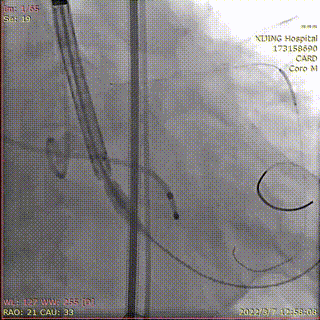

送入26mmVenus-A Plus造影定位

释放1/3瓣膜造影检查位置

释放2/3瓣膜

造影检查位置

完全释放Venus-A Plus

烟囱支架扩张释放

术后造影显示瓣膜位置理想,冠脉充盈正常